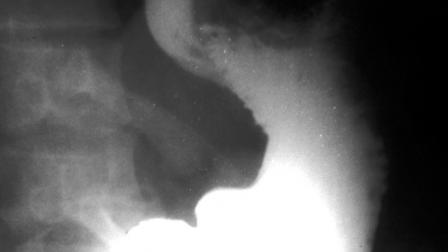

Previo a la operación los doctores realizaron una radiografía para determinar la cantidad de objetos en su estómago , así que se logró determinar piezas metálicas de hasta 10 centímetros